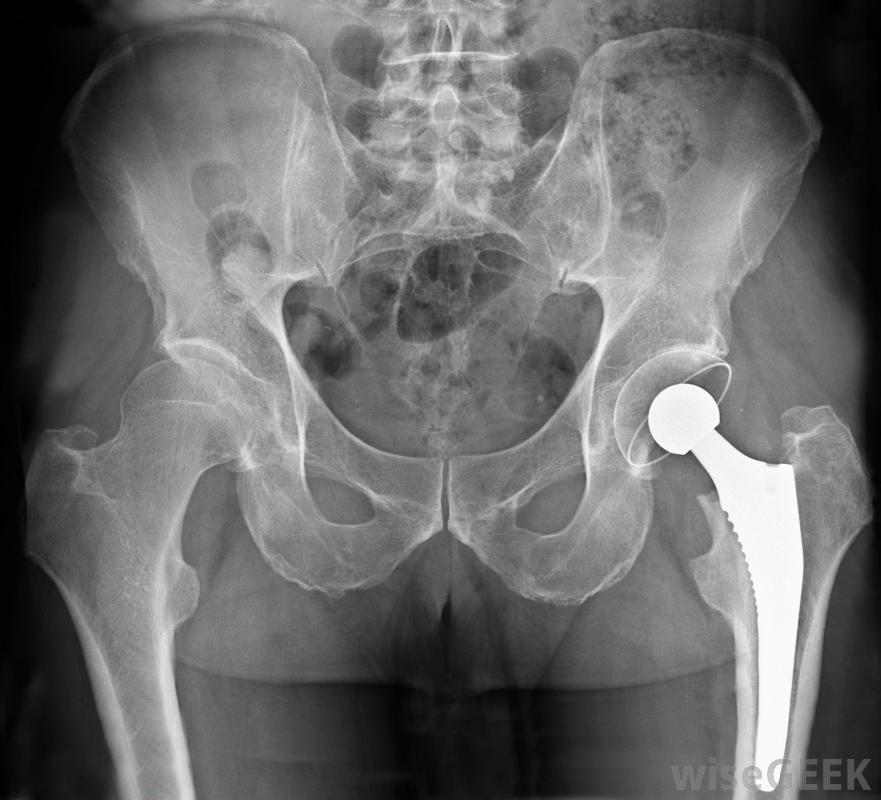

骨科植入物是植入骨骼和关节以恢复正常功能的人工装置。通常,当髋关节、膝关节、肩关节或肘关节因损伤或骨关节炎等疾病而受损时,骨科植入物起到关节置换的作用,关节磨损会导致疼痛和僵硬植入物通常只在非手术治疗方法失败的情况下使用。植入物往往会在数年后磨损,因此,给年轻人使用的植入物在某些时候可能需要更换。骨科植入物可以帮助患有骨关节炎的人增加他们的活动性。许多不同的材料被用来制作骨科植入物,包括塑料,陶瓷和金属,如不锈钢和钛。植入物可以通过多种方式固定到位。可以使用水泥或螺钉固定,也可以通过周围环境的压力将其固定到位。通常,从矫形植入物周围生长的骨可以帮助固定。有时,植入物的一部分在另一部分没有骨水泥的情况下,如髋关节置换术,称为混合型髋关节,其中承载关节球形部分的柄可以用水泥固定,而接收杯则不是骨盆区域的X光片,显示一个金属置换髋关节钛制骨科植入物具有强度高但重量轻的优点,而且人体通常不会对其产生反应。缺点是,骨细胞很难粘附在金属的闪亮表面上,因此在愈合过程中很难与骨融合。研究进展正在寻找新的蚀刻方法一种称为纳米管的微型管进入钛表面,这是一种以前成本太高而不实用的方法。这些纳米管的结构使它们对水具有吸引力,并为细胞的生长提供了一个合适的环境虽然骨科植入物有好处,如增加活动性和减少与损伤或退行性关节疾病相关的疼痛,但偶尔也会出现一些缺点。植入物可能会松动或断裂,身体很少会对其产生反应。有时可能会发生感染,这使得有必要更换植入物。细菌可以在骨科植入物的表面生长,形成所谓的生物膜,要解决这个问题,必须在安装替代物之前移除植入物并治疗感染。对所谓的水凝胶的研究可能会给未来带来希望,由于这些吸水性物质对细菌不友好,同时仍允许骨细胞生长,因此可以将它们添加到植入物表面,以尽量减少感染的机会。